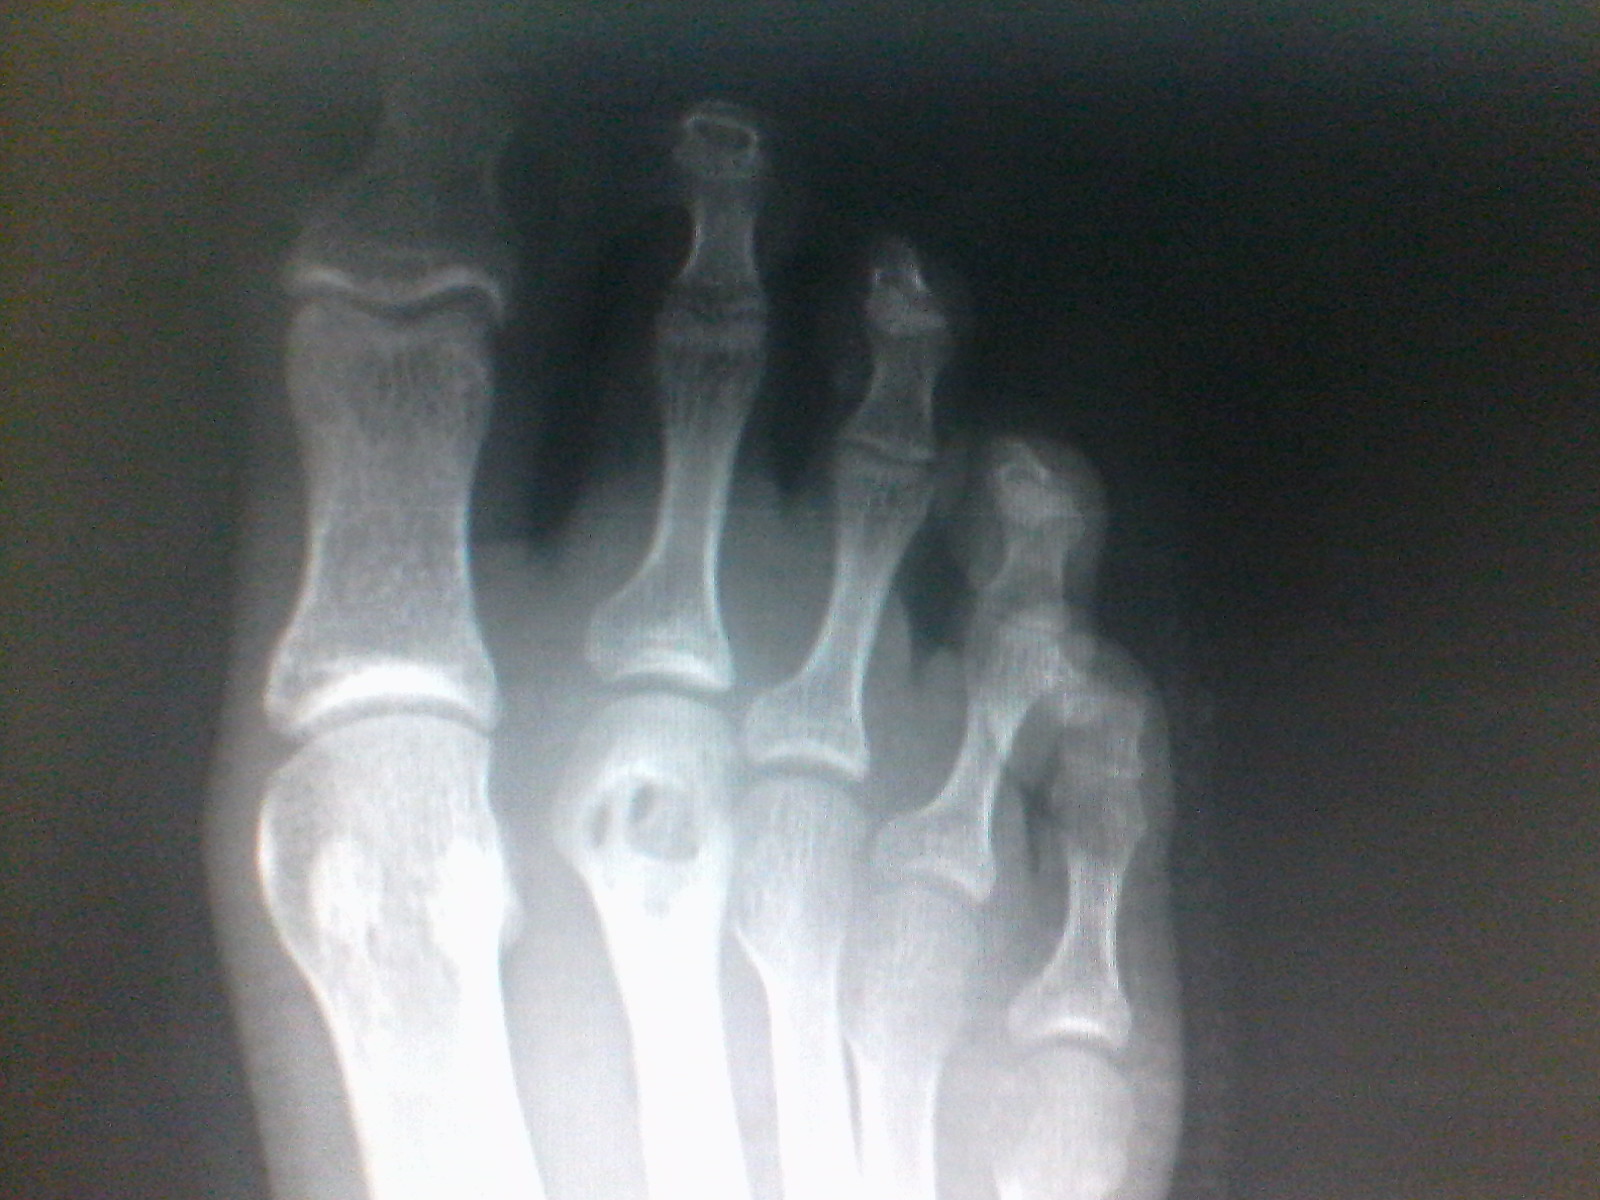

Rx de pie

Dicho objeto extraño se había introducido en el pie del joven mientras caminaba en un tejado, sin embargo este no entro allí por si solo, fue empujado por un clavo que piso el paciente y se enterró justo en la parte distal del segundo metatarsiano. Dicho objeto era un trozo de goma del calzado que llevaba el adolescente.

Como puede observarse el hueso donde se introdujo el objeto quedo perforado y sorprendentemente sin fractura aparente.

Los huesos tienen la propiedad de regenerarse así que el joven deberá mantener reposo mientras que su metatarsiano se vuelva mas fuerte y ya no corra riesgo de empeorar la lesión.